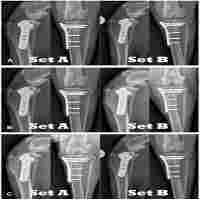

| Abstract | Background Little is known about the weight distribution to the remaining limbs for amputee dogs that undergo orthopedic surgery. The objective of the paper was to describe stance and weight distribution after tibial plateau leveling osteotomy (TPLO) in forelimb and in hind limb amputees (AmpTPLO) and to compare them to four-legged TPLO patients (4LTPLO) and amputees without TPLO (Amp). Weight bearing distribution at a stance was compared between groups. Joint angles of forelimb and hind limb joints in a sagittal plane, hind limb orientation in a frontal plane, and pelvic orientation in a transverse plane (pelvic tilt) were measured and compared between groups. Results Joint angles, hind limb abduction, and pelvic tilt of AmpTPLO and Amp did not differ statistically. Mean weight bearing in the operated hind limb was higher for AmpTPLO than 4LTPLO. Mean weight bearing for thoracic limbs of AmpTPLO and 4LTPLO did not differ statistically. Weight bearing of the hind limb of AmpTPLO and Amp did not differ statistically. Conclusions The position of the center of mass and posture of AmpTPLO and Amp does not differ. The weight distribution and posture of Amp is not impacted negatively by TPLO. |